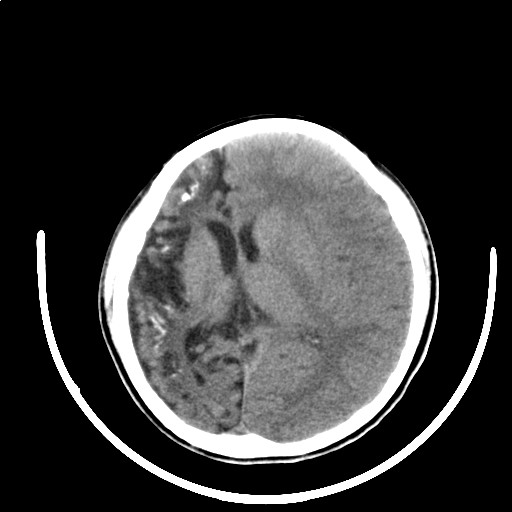

标题: PED3416:F,12Y,智力下降,学习成绩差,8个月时发过高烧。

右侧大脑发育不良伴动静脉畸形。

右侧半球萎缩,软化,多量脑回样钙化,考虑颅面血管瘤病,建议dsa检查

右侧半球萎缩,软化,多量脑回样钙化,同侧颅盖板障增宽,考虑颅面血管瘤病,建议dsa检查与化脓性脑膜炎后遗改变鉴别。